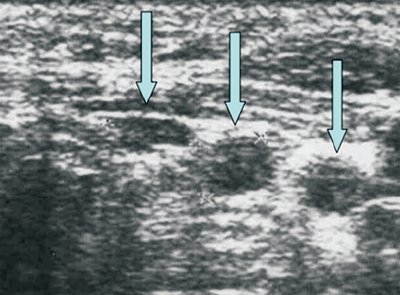

Достаточно характерная ультразвуковая картина лимфатических узлов наблюдается при лимфогранулематозе. При этом в большинстве случаев видно несколько увеличенных лимфатических узлов (одна или несколько групп лимфатических узлов). Узел имеет овальную или округлую форму, четко видимую капсулу, гомогенную, чаще слабо гипоэхогенную структуру. Группа увеличенных лимфатических узлов ("пачка") представлена четко отграниченными, не прорастающими капсулу и не сливающимися между собой лимфатические узлы (как при метастатическом поражении, в виде конгломерата) и может локализоваться в какой-либо одной области (например, надключично справа или слева) или в нескольких областях (увеличенные лимфатические узлы средостения, надключичные и в нижней трети шеи с одной или обеих сторон и др.).